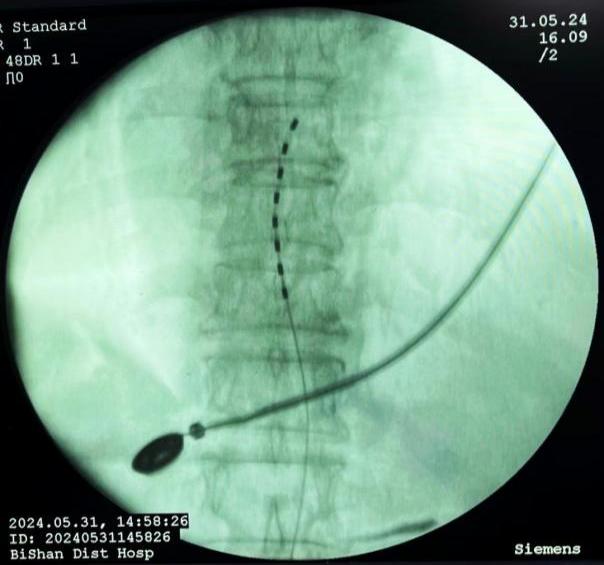

3.癌痛規(guī)范化管理:癌痛是癌癥患者最常見和難以忍受的癥狀之一,不僅嚴(yán)重影響患者的睡眠、飲食,而且加重患者心理負(fù)擔(dān),導(dǎo)致焦慮、抑郁等,嚴(yán)重影響患者的生活質(zhì)量。癌痛的治療方法包括:病因治療、藥物止痛治療和非藥物治療。癌癥患者常面臨難以控制的疼痛,傳統(tǒng)的藥物治療在這些患者中可能效果有限或伴隨嚴(yán)重副作用??剖以阼瞪降貐^(qū)率先采用了鞘內(nèi)藥物輸注(Intrathecal Drug Delivery, IDD)進(jìn)行癌痛管理,通過將藥物直接輸送到脊髓鞘內(nèi),可以顯著提高藥物的局部濃度,從而增強(qiáng)鎮(zhèn)痛效果并減少全身副作用。

鞘內(nèi)泵植入術(shù)